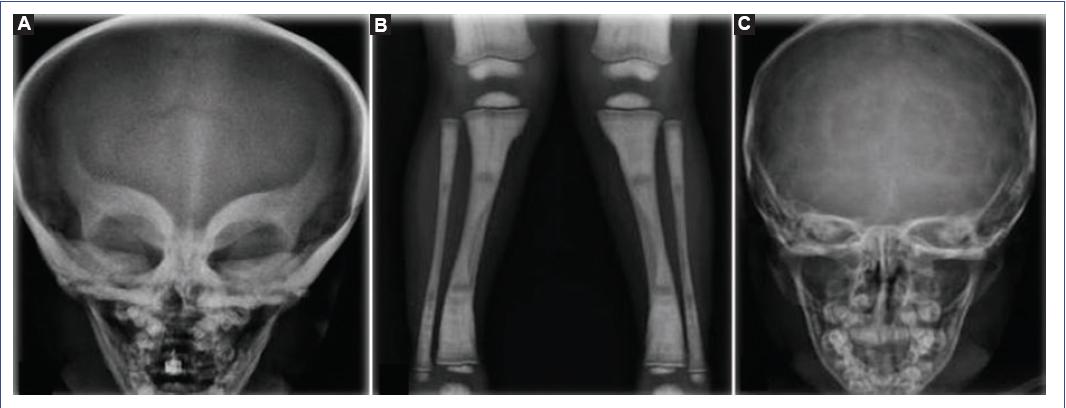

At 3 years of age, he was admitted again for CAP. On physical examination, generalized integument paleness, macrocephaly, hypertelorism, microretrognathia, prominent forehead, telecanthus, trichiasis, prominent eyes, flat nasal bridge, short neck, and narrow chest were observed. The skull X-ray showed the mask sign, characterized by generalized bone hyperdensity, predominantly at the base of the skull, which gave it the appearance of a mask in the orbital region. A chest X-ray was performed, observing an increase in bone density at the rib, sternal, and vertebral level. In addition, the bone within a bone sign, which consists of lines parallel to the tibia’s cortical bone, was observed in the long bone X-ray. In laboratory studies, bicytopenia was reported in the complete blood count (hemoglobin 5.7 mg/dl, hematocrit 17.7%, leukocytes 13,400 cells/μL, total neutrophils 4020 cells/μL, and platelets 22,000 cells/μL). Therefore, as part of the approach, a bone marrow biopsy was requested, which reported hypocellularity, small intertrabecular spaces with fibrous tissue, and endochondral ossification. Due to the presence of dysmorphic syndrome, the patient required evaluation by the genetics service.

Infantile osteopetrosis is a rare hereditary disease, with a characteristic phenotype of short stature, hypocalcemia, fractures, compression neuropathy, and pancytopenia; it is caused by the failure in the development and function of osteoclasts. We present the case of a 5-year-old male with a CLCN7 gene mutation and a 1-year follow-up after Allo-HSCT. Because osteopetrosis is caused by a defect in the osteoclasts derived from the hematopoietic cell line, bone marrow transplantation is the definitive treatment. Our patient underwent Allo-HSCT at 3 years and 9 months of age and currently has normal cell counts. The skeletal deformities and bone sclerosis shown on the X-rays improved since treatment (Fig. 3). Since the first approach, this patient exceeded the 3-year life expectancy reported for osteopetrosis patients with the CLCN-7 mutation (Table 1). Over 600 days after the transplant, the patient has shown a favorable evolution, decreasing the need for transfusions and hospitalization. Furthermore, skeletal deformities and neurodevelopmental tests have improved, leading to a better quality of life.

Figure 3 Osteopetrosis patient imaging studies. A. X-ray of the skull showing mask sign. Predominant generalized bone hyperdensity is observed at the base of the skull (before transplantation). B. X-ray of tibia and fibula with the bone within a bone sign. C. X-ray of the skull after transplantation with decreased bone hyperdensity.